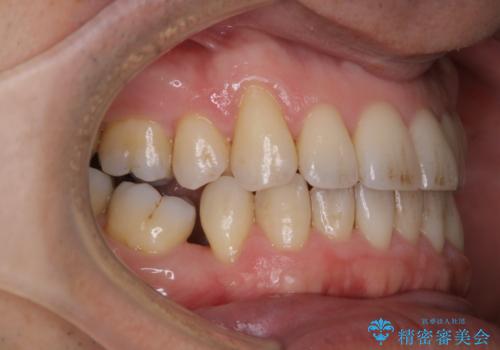

紅茶のステインをきれいにしたい

- 毎日紅茶を飲むため、歯のステインが気になるためキレイにしたいとのことでした。

PMTC60分コースを行いました。